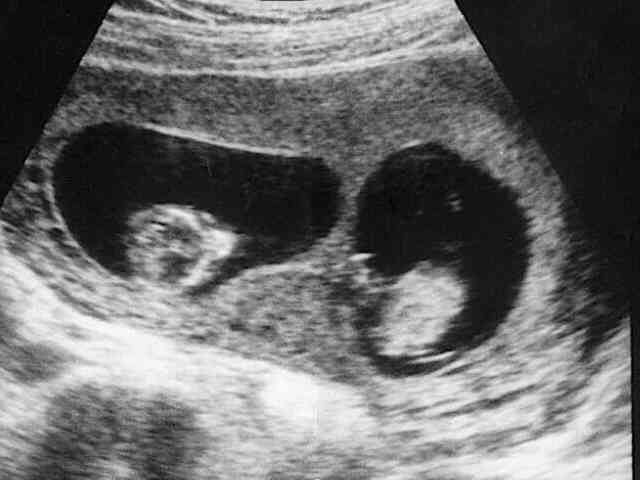

amh0.06做試管嬰兒的成功率比較低,在試管嬰兒過程中,主要面臨的問題是無卵可取,即使進行好的促排卵治療,由於每個女性的身體狀況的不同,對於amh0.06的女性來說,能否取出卵與自身年齡和身體機能有較大的關係。但是隻要amh沒有因為年齡因素而降低,並且降低值不是很嚴重,可以通過注意飲食,服用藥物、運動鍛鍊、保持良好的情緒來改善。amh值是判斷女性卵巢儲備功能的指標之一,在各個年齡階段,amh偏離正常值,都意味著女性卵巢正在衰退和老化,如果不加以治療,女性卵巢的儲備功能會迅速退化,嚴重影響女性的生育能力,其實在日常生活中,有4種方法可以提高amh值,分別是注意飲食、使用藥物、加強鍛鍊、保持良好的情緒。

amh0.06做試管嬰兒的成功率比較低,在試管嬰兒過程中,主要面臨的問題是無卵可取,即使進行好的促排卵治療,由於每個女性的身體狀況的不同,對於amh0.06的女性來說,能否取出卵與自身年齡和身體機能有較大的關係。

除此之外,amh值為0.06的女性做試管的成功率,還取決於女性卵巢的基礎竇卵泡及基礎的fsh資料,如果竇卵泡很少或fsh過高,不建議做試管嬰兒。如果女性卵巢內仍有一定數量的竇卵泡基礎和fsh基本正常,還是可以考慮做試管嬰兒的。